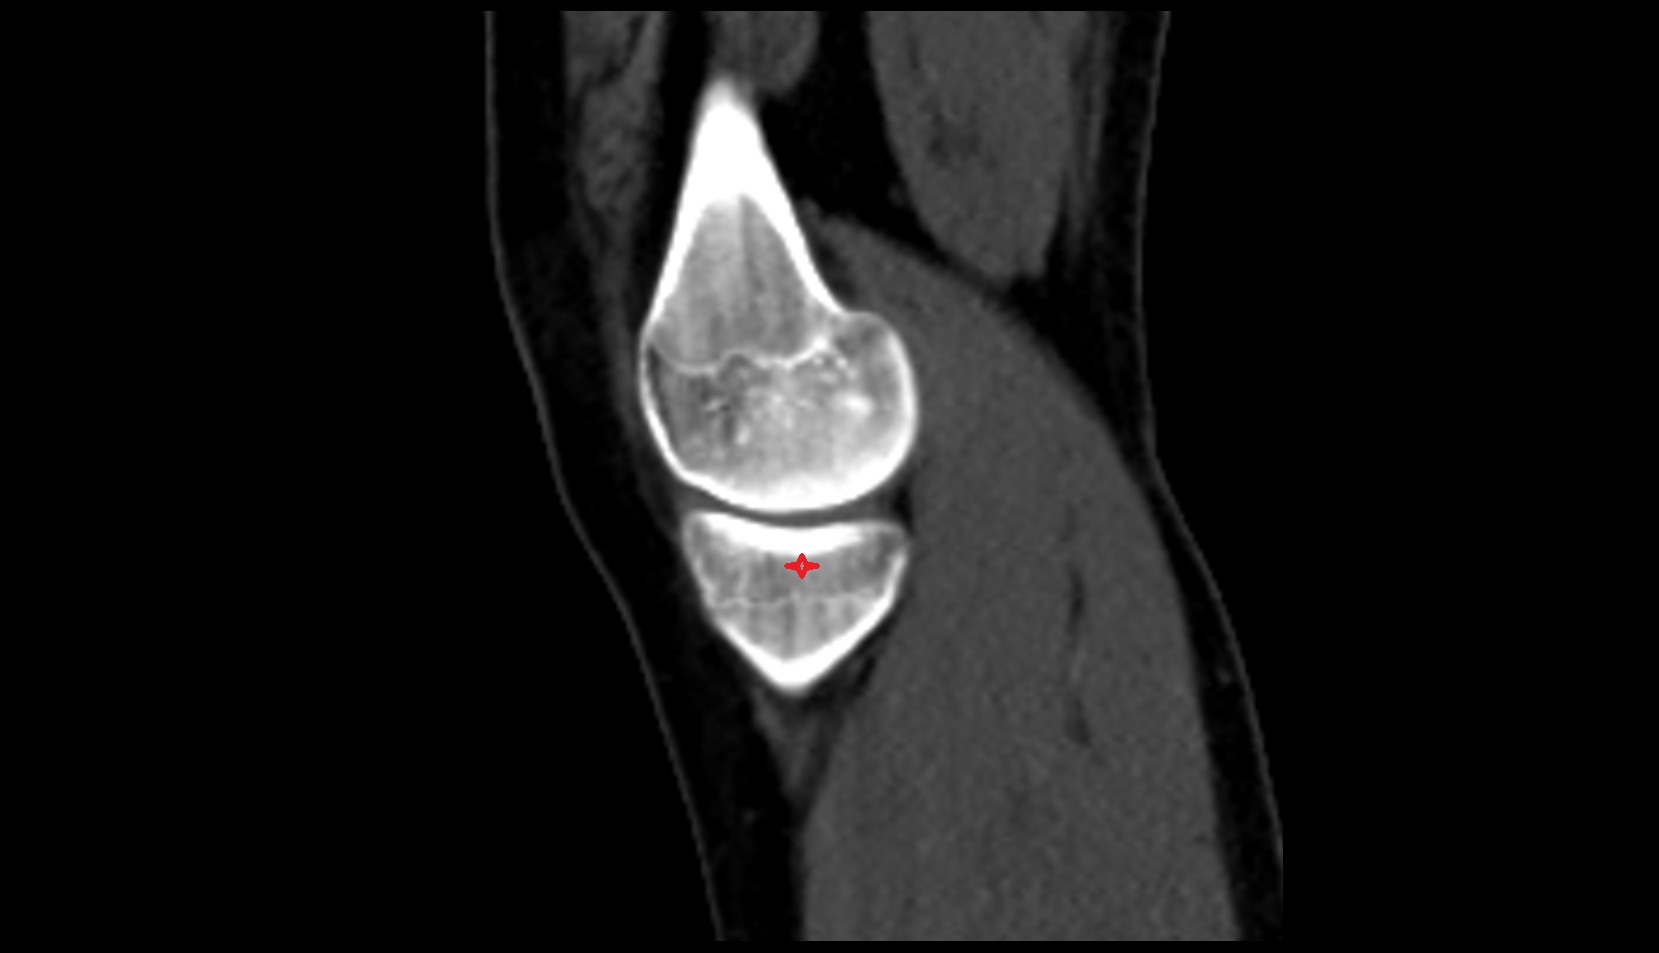

- Knee Joint

- Lateral condyle of femur

- Medial condyle of femur

- Medial tibial plateau

- Lateral tibial plateau